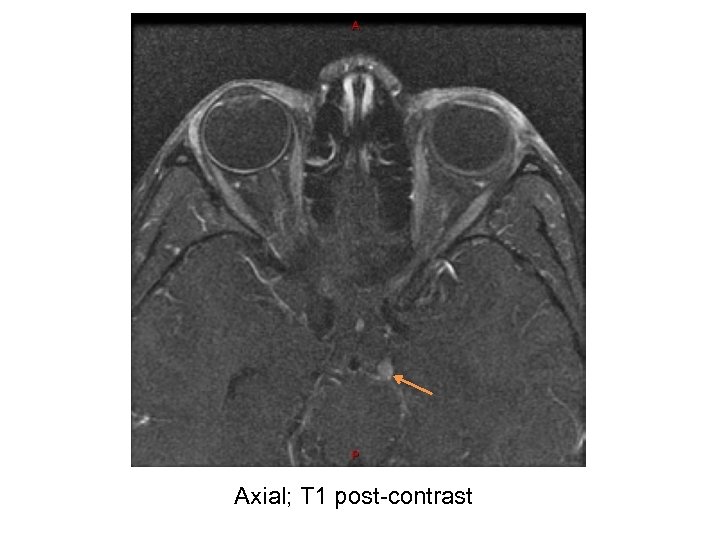

Our Patient – Diagnostic tests • MRI Brain – No obvious radiological abnormality • MRA Head and Neck – Normal • MRI Orbit (w/wo contrast): – At the left interpeduncular fossa between the left P 1 segment and superior cerebellar artery there is an enhancing 4 mm focal, round lesion involving the proximal left oculomotor nerve favored to represent a schwannoma. No connection to the vasculature seen.

Axial; T 1 post-contrast